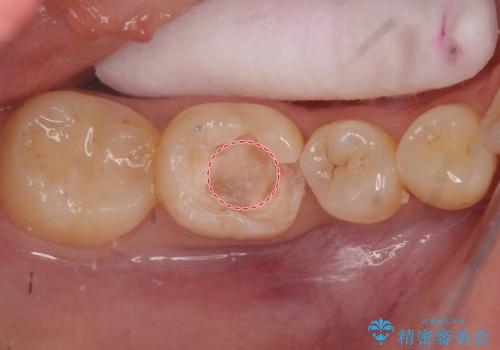

欠けた詰め物をすべて取り除くと深いところに取り残された虫歯を発見しました。

虫歯の除去後は残った歯の厚みが薄くなっていたため、今後の破折リスクを考慮してクラウンでの修復処置となりました。

虫歯が深く歯の神経の炎症が予想される箇所には鎮静作用のあるセメントを敷き、経過をみた後に被せ物をセットしました。